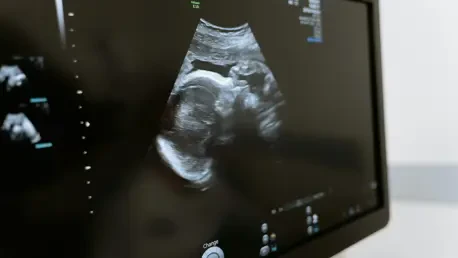

Covid in Pregnancy Linked to Child Development Risks?

I’m thrilled to sit down with Dr. James Maitland, a renowned expert in maternal-fetal medicine and neurodevelopmental research at Massachusetts General Hospital. With a deep commitment to understanding how prenatal exposures impact child development, Dr. Maitland has been at the forefront of groundbreaking studies, including recent research on the potential link between COVID-19 during pregnancy and neurodevelopmental outcomes in children. Today, we’ll explore the nuances of this connection, the biological mechanisms at play, and what this means for parents and healthcare providers navigating the aftermath of the pandemic.